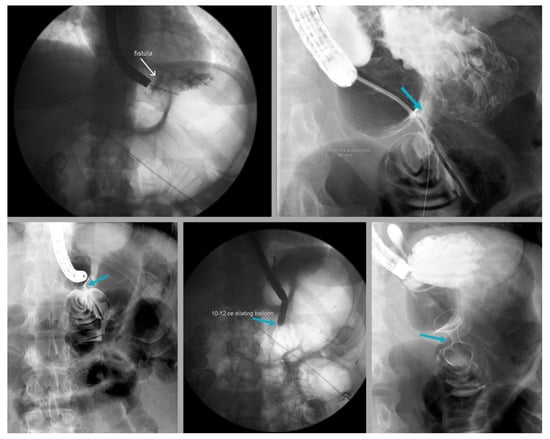

- Chang, S.H.; Popov, V.B.; Thompson, C.C. Endoscopic balloon dilation for treatment of sleeve gastrectomy stenosis: A systematic review and meta-analysis. Gastrointest. Endosc. 2020, 91, 989–1002.e4. [Google Scholar] [CrossRef]

- Dhorepatil, A.S.; Cottam, D.; Surve, A.; Medlin, W.; Zaveri, H.; Richards, C.; Cottam, A. Is pneumatic balloon dilation safe and effective primary modality of treatment for post-sleeve gastrectomy strictures? A retrospective study. BMC Surg. 2018, 18, 52. [Google Scholar] [CrossRef]

- Kurien, R.; Menon, S. Balloon dilation in sleeve gastrectomy stenosis: A simple solution to an occasionally tricky problem. Gastrointest. Endosc. 2020, 91, 1003–1004. [Google Scholar] [CrossRef]